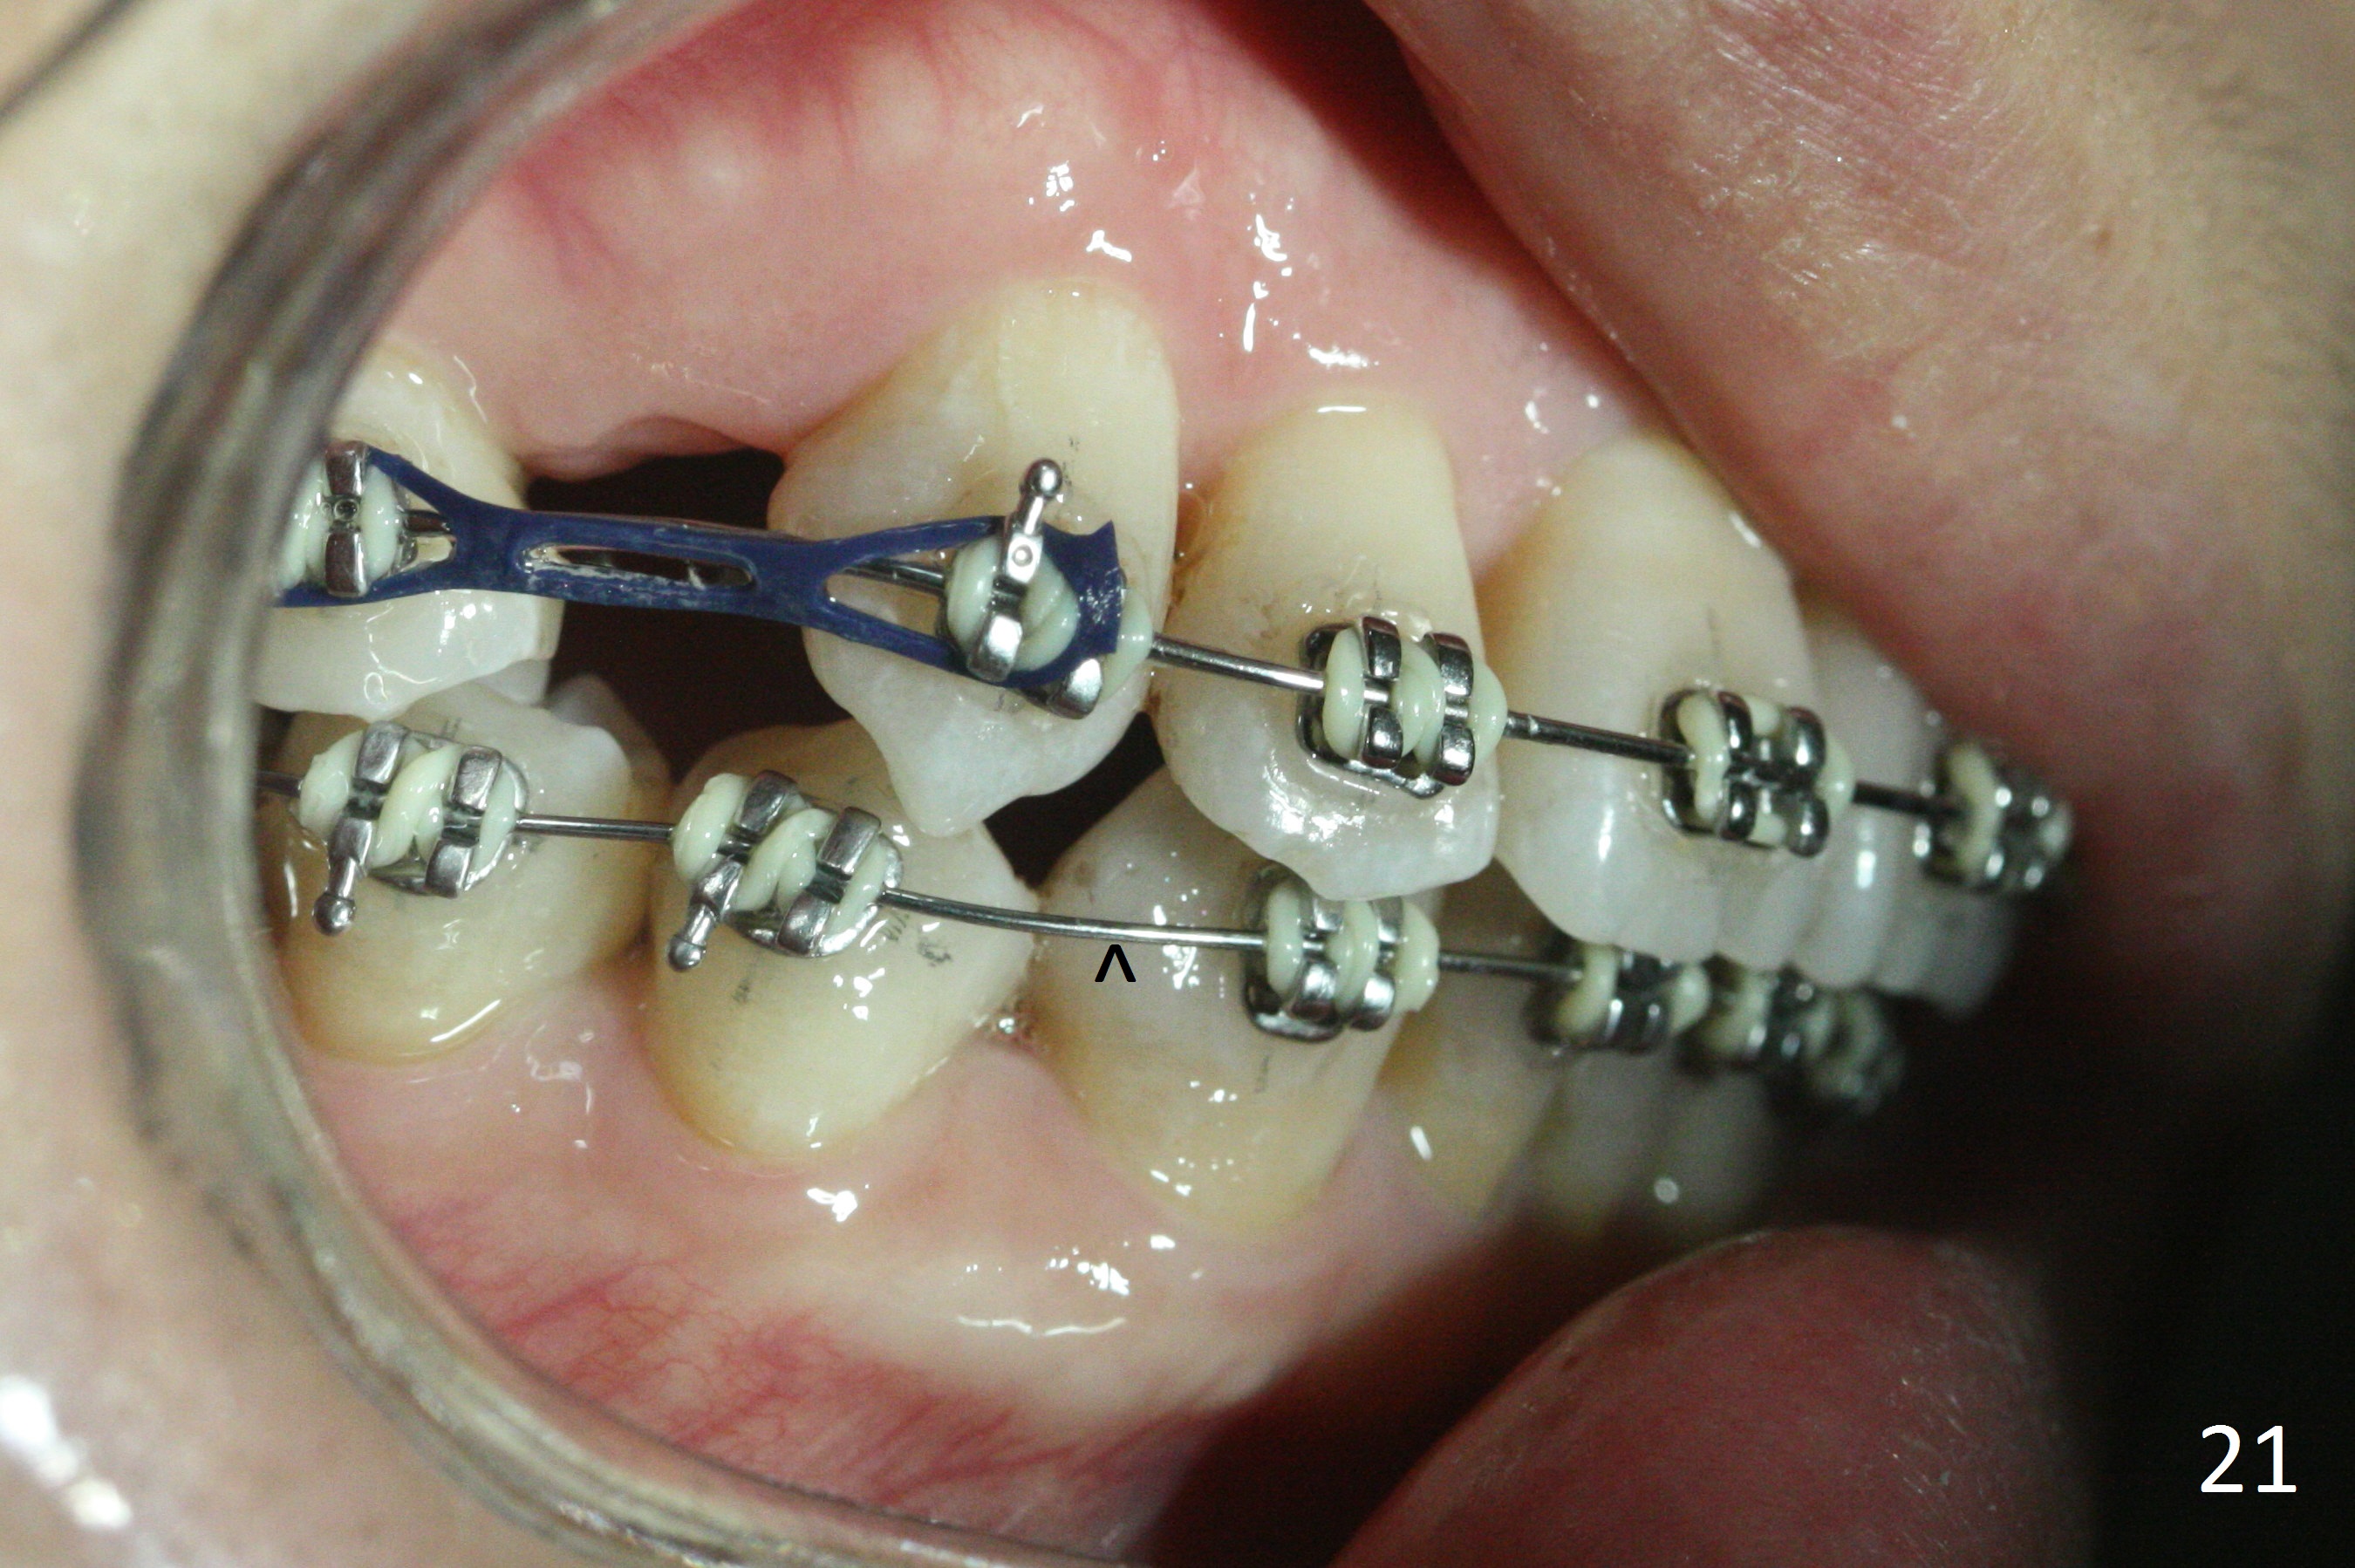

The rotation of the upper canines is not corrected much in the next 3.5 months (Fig.21, as compared to Fig.18). Distalization of the upper right canine is implemented by power chain, but this is not sufficient because of the anterior deep bite. Note the tension of 18 niti wire between LR 3 and 4 (^). Mini implants are going to be placed mesial or distal to L3s (Fig.22,23 circles) to intrude the lower anterior teeth with elastic or power chain (Fig.23 red line, 24 black area). The upper anteriors will have space to be distalized (Fig.24 arrow). If necessary, proximal reduction will be accomplished at LR3 (extra wide, Fig.25 black outline) for further overjet correction (arrows).